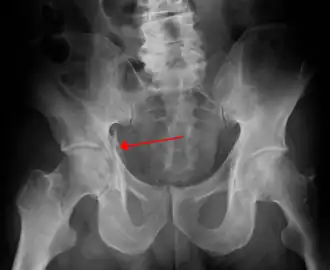

![]() Radiografía en la que puede visualizarse una fractura de acetábulo | ||

La fractura de acetábulo o fractura de cavidad cotiloidea, es un tipo de fractura ósea que afecta a la cavidad cotiloidea en la pelvis. No debe confundirse con la fractura de fémur, en la fractura de acetábulo el fémur permanece indemne, salvo que exista lesión combinada.[1]